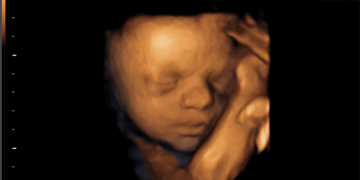

Today marks the 58th anniversary of the Abortion Act coming into effect in 1968 – six months after it received Royal Assent. Since then, a staggering 11,105,671* unborn babies have lost their lives to abortion across the UK. At the current rate…